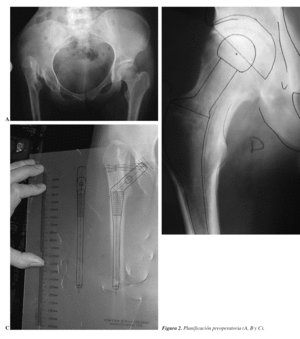

Son las primeras que hay que tener en cuenta y consisten en realizar una correcta planificación con las plantillas (figs. 2 y 3), con el fin de reproducir el acodo lo más exactamente posible, el centro de rotación de la cadera y la longitud del miembro9-12. Los pasos conocidos, pero que conviene recordar, son los siguientes:

Radiografías necesarias:

1. Anteroposterior de pelvis con el foco en la sínfisis pubis.

2. Anteroposterior de la cadera a intervenir y que se vea 20 cm de fémur.

3. Proyección lateral o axial.

Pasos:

1. Datos del paciente, diagnóstico, lado a intervenir y tipo de implante.

2. Sobre la radiografía anteroposterior (Rx AP) de pelvis se traza una línea horizontal que una ambas tuberosidades isquiáticas, comprobando que comprende ambas corticales femorales.

3. Marcar en la misma Rx el punto más proximal de ambos trocánteres menores.

4. Medir la distancia desde el punto proximal del trocánter menor a la línea biisquiática. Cuanto mayor sea la distancia más corta estará la pierna. Si se presenta esta situación hay que anotar la diferencia de longitud de los miembros inferiores.

5. Sobre la radiografía anteroposterior de la cadera se determina el tamaño apropiado, la posición y componente acetabular con las plantillas; después se marca el centro de rotación de la cadera.

Desde el punto de vista práctico, una planificación quirúrgica sería:

1. Nombre, apellidos y número de historia.

2. Edad y sexo.

3. Diagnóstico, tipo de implante cementado (sí/no, mixto).

4. Diferencia, si existe, de longitud de los miembros inferiores (MMII).

5. Cotilo: diámetro en mm, hemisférico, monobloque, perforado, insertos polietileno, cerámica, metal, tamaño interior.

6. Vástago: offset, número, si está cementado o no.

7. Corte del cuello a xx mm por encima del trocánter menor.

8. Longitud del cuello de más de 3,5 mm de diámetro; cabeza en mm metálica/cerámica.

9. Con esta reconstrucción se alarga o no el miembro.

10. Equipo especial que se puede necesitar: a) cotilos y fresas más pequeñas de lo habitual; b) cabezas de 26 mm de diámetro si hubiese que utilizar cotilos pequeños; c) cables de Dall-Miles o material de osteosíntesis en caso de fractura; d) instrumental específico para extraer implante; cortar cerámica, etc.